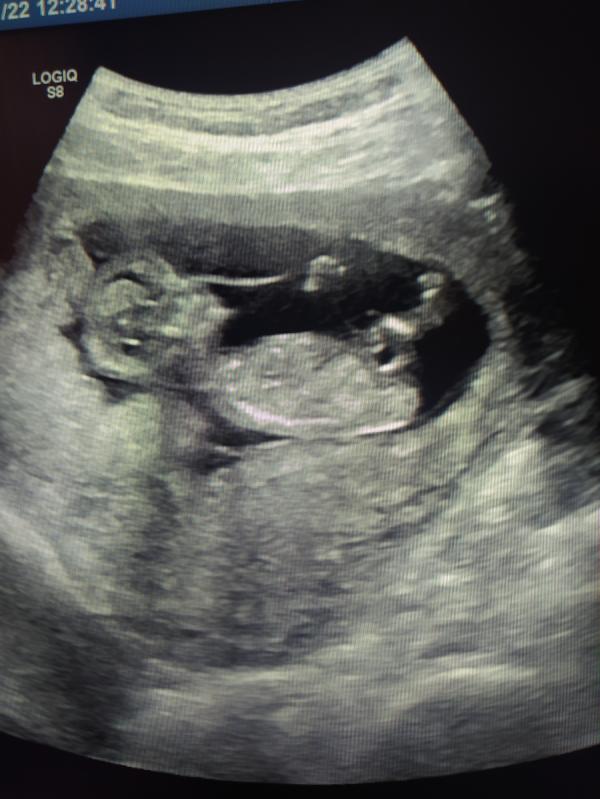

Всем привет! 12 недель, на узи предположили мальчика, а так хочется девочку 😀 слышала наоборот предполагают девочку, а потом писюлька выростает) А с мальчиком всё уже, не рассосётся?😅 Было ли у кого что мальчик на 2 скрининге оказывался девочкой?

Пусть будет как бы вам хотелось 🙏😊 а я надеюсь в нашем случае не чего там не дорастет 😅 я так понимаю на моём сроке там у всех одинаково, смотрят только под каким углом)

Мне на 12 сказали мальчик, потом выяснилось на 18 неделях девочка, оказывается у них в утробе бывает гипертрофия клитора и похоже на пенис